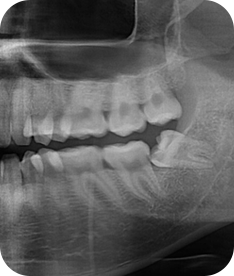

사랑니 발치

청담네오플란트는 3D CT 촬영 후 전문의료진들의 정확한 분석으로 안전하게 사랑니를 발치합니다.

매복 사랑니 발치 이젠 두려워하지 마세요!

청담네오플란트치과 사랑니 발치 프로세스

01. CT 촬영

안전하고 통증을 최소화한 발치를 위해 3차원 정밀 분석을 합니다.

02. 정확한 분석

사랑니의 크기와 방향, 깊이, 뿌리 상태 등과 구강검진을 실시합니다.